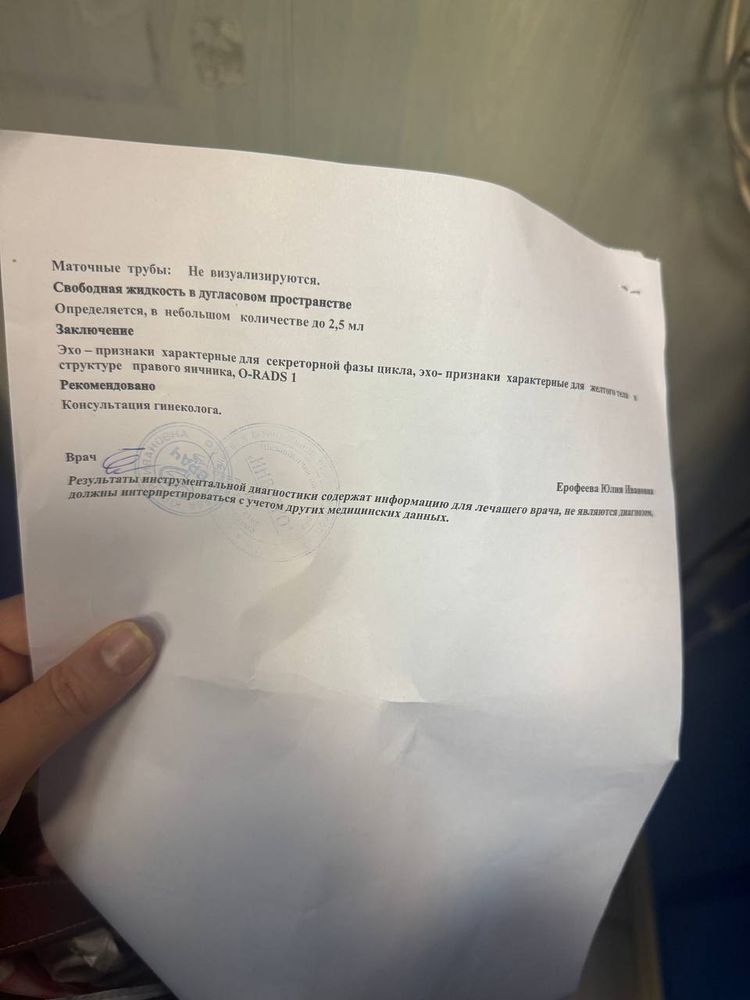

Девочки,помогите пожалуйста. Я третий цикл принимаю инозитол, на двух циклах овуляция была на 18ДЦ, в этот раз пошла на УЗИ на 17ДЦ и врач сказала ,что видит хорошее ЖТ и что овуляция уже была,конечно примерно когда она была не может сказать. У меня сейчас идет 34 ДЦ, грудь ужасно болит, всю неделю подтягивал низ живота как будто сейчас польет и белые выделения. Но,месячных нет( сделала тест вечером он показал одну полоску( конечно наверное лучше делать тесты утром). Не могу понять, что со мной. Может у кого так было ?